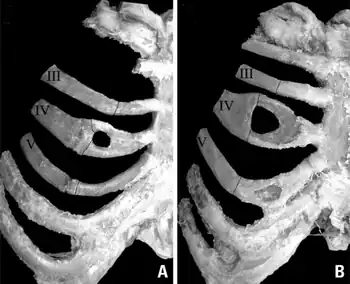

![]() | |

| Bifid rib at the right side seen on chest radiograph. The fourth rib splits in two towards the sternal end. | |